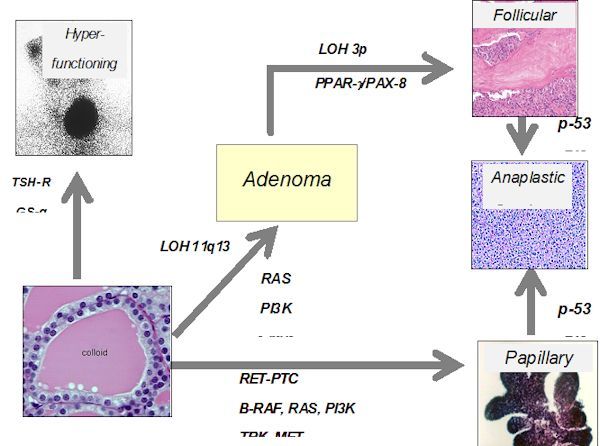

Thyroid Cancer Explore vol.3 no.2(2201 「Thyroid Cancer Expl Thyroid Cancer Treatment (PDQ®) - NCIの詳細情報

Thyroid Cancer Treatment (PDQ®) - NCI。Comparative Analysis of Metastatic Thyroid Carcinoma versus。The Role of Positron Emission Tomography/Computed Tomography。

Thyroid Cancer - Endotext - NCBI Bookshelf

Thyroid Cancer - Endotext - NCBI Bookshelf